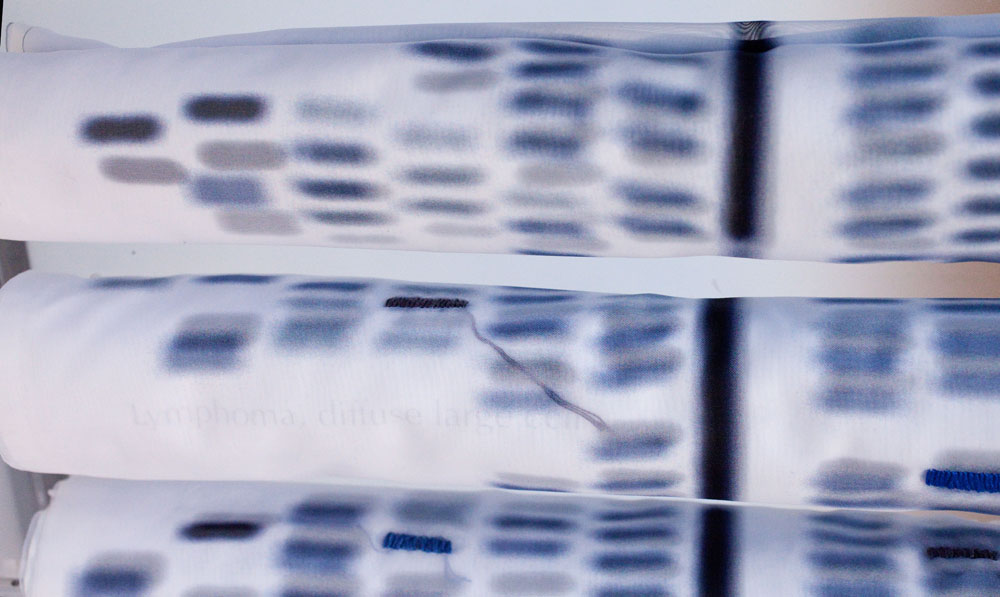

CASE STUDY 22 CHROMOSOMES X & Y, 2011

Front panel: Jacquard dye and hand embroidery on dye sublimation, printed sheer silk. Back panel: Laser-printed linen, 20” x 9’

Laser-cut plexiglass box, steel stand. Open 36” x 40” x 24” x 10”, closed 24” x 40”

Collection: The Portland Art Museum

Case Study delineates the human genome, organized into 22 human autosomal chromosomes, the two sex chromosomes X and Y, and corresponding genetic markers and identification, using the NCBI database. In this piece, graphic genetic representations of chromosomes are printed onto sheer synthetic silk, accompanied by the names of genes linked to discernible traits and genetic diseases present in my own extended family. The 24 scrolls are each made of a layer of ultra-sheer silk on top of linen and printed with the graphic representation for all 24 human chromosomes. The cloth has been digitally printed, hand-painted and selectively embroidered to highlight markers on each chromosome. Those highlighted parallel the location of various qualities and anomalies. Each cloth representation of the chromosome is rolled and housed within a large closeable case inscribed with Case Study. The total presentation is meant to appear like the casing for religious scrolls kept in storage for future reading. The scrolls represent the genetic archive that is in each of our bodies. I have highlighted the qualities of the past generation as well as the present.

Technological advances allow us to sharpen our focus on inner physical worlds, learning to read genetic markers to the point of being able to predict human developmental outcomes. Case Study is inspired by such research. The 24 scrolls of ultra-sheer synthetic silk represent all the human chromosomes, but their soft ethereality suggests a transparent veil that cloaks even as it reveals. Like skin, a veil is a thin layer on top of a body; it hides, protects, and gives an illusion of the softened form below. In this work the veil-like scrolls are used to present—and mask—layers of information, some of it potentially catastrophic. Though deeply immersed in scientific image making, Ondrizek melds current textile technology with age-old handcraft. She meticulously hand dyes the panels with Jacquard silk dyes after they have been digitally printed, then selectively embroiders blocks in the chromosome panel with silklike cotton thread.

Equivalents are prevalent in Ondrizek’s work; the colors, textures, and forms in art and science begin to define each other by example, one in relationship to another. The blue tone on the scrolls is altered from the original digital rendering, made softer for purely aesthetic reasons. Her intent was to place the gray tones on the back panel to suggest a monochromatically printed scientific report and to place the blue “veils” in front, to represent matter tinted for examination. The hidden layer of subtly gray-printed muslin has the respective disease delicately written on each chromosome pattern. The color of the embroidery thread on the outer panel derives from the intense blue of the actual test result from the National Institutes of Health. Genes holding hereditary probability for disease appear darker in the scientific print of the chromosomes, so the artist ominously chose to embroider random blocks with a dark blue thread, an aesthetic decision that mimics meaning.

Scrolls: Chromosome images are from the Human Genome Overview, National Institutes of Health’s National Library of Medicine.